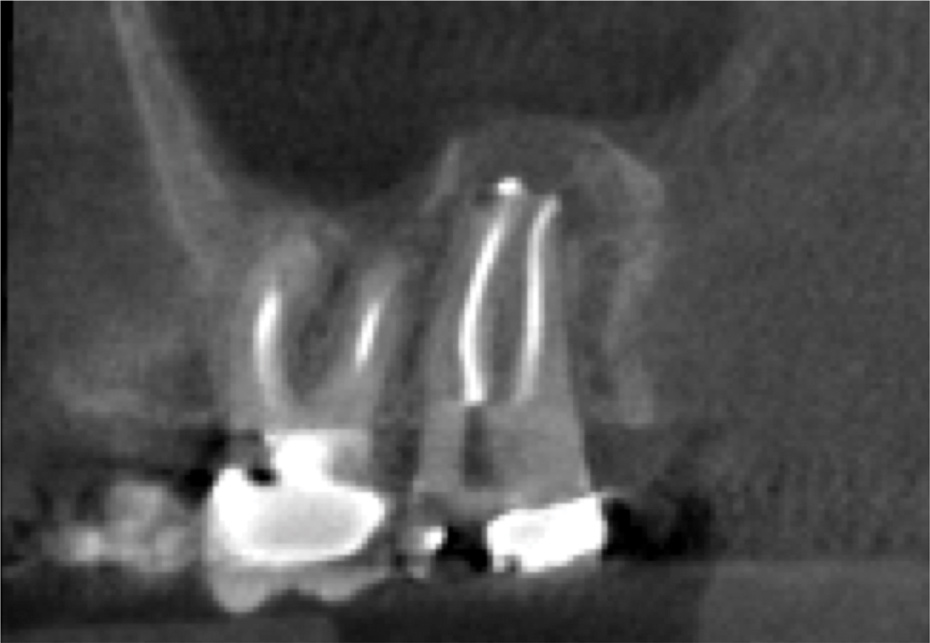

For patients suffering from MSEO, radiographs will reveal a periapical radiolucency with adjacent opacification in the maxillary sinus.12 Additional radiographic findings associated with MSEO include periapical mucositis and periapical osteoperiostitis (PAO). Periapical mucositis refers to mucosal thickening or dome-shaped soft-tissue expansion on the floor of the sinus directly adjacent to the infected root apex.PAO refers to the reactive osteogenesis caused by a local periosteal reaction that expands the sinus periosteum and displaces it upward into the sinus. It appears as a radiopaque "halo" surrounding the root apex (Figure 2 through Figure 4). PAO may be symptomatic and/or accompanied by adjacent mucosal edema and elevated sinus fluid levels.9 If left untreated, PAO can progress and result in a direct communication between the root apex and maxillary sinus.6,13 Unless bilateral odontogenic pathosis is found, the sinus opacifications will usually be unilateral and centered around the odontogenic source. Complete unilateral sinus opacifications may be missed on the CBCT images typically used in endodontics due to their limited or focused field of view (Figure 5). In cases involving complete unilateral sinus opacification, referral to an ENT or oral surgeon is essential to rule out invasive fungal infection or malignancy.2,17,24

(4.) Coronal slice of CBCT image of the same tooth.

Figure 4